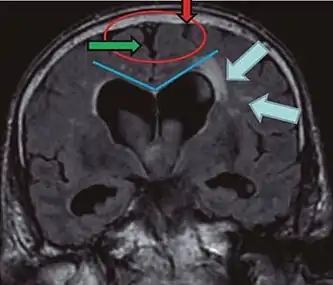

- Imaging from magnetic resonance imaging (MRI) or computed tomography (CT) is needed to demonstrate enlarged ventricles and no macroscopic obstruction to cerebrospinal fluid flow. Imaging should show an enlargement to at least one of the temporal horns of lateral ventricles, and impingement against the falx cerebri resulting in a callosal angle ≤ 90° on the coronal view, showing evidence of altered brain water content, or normal active flow (which is referred to as "flow void") at the cerebral aqueduct and fourth ventricle.

| Normal pressure hydrocephalus | Brain atrophy | |

| Preferable projection | Coronal plane at the level of the posterior commissure of the brain. | |

| Modality in this example | CT | MRI |

| CSF spaces over the convexity near the vertex (red ellipse | Narrowed convexity ("tight convexity") as well as medial cisterns | Widened vertex (red arrow) and medial cisterns (green arrow) |

| Callosal angle (blue V) | Acute angle | Obtuse angle |

| Most likely cause of leucoaraiosis (periventricular signal alterations, blue arrows |

Transependymal cerebrospinal fluid diapedesis | Vascular encephalopathy, in this case suggested by unilateral occurrence |

MRI scans are the preferred imaging. The distinction between normal and enlarged ventricular size by cerebral atrophy is difficult to ascertain. Up to 80% of cases are unrecognized and untreated due to difficulty of diagnosis.[10] Imaging should also reveal the absence of any cerebral mass lesions or any signs of obstructions. Although all patients with NPH have enlarged ventricles, not all elderly patients with enlarged ventricles have primary NPH. Cerebral atrophy can cause enlarged ventricles, as well, and is referred to as hydrocephalus ex vacuo.